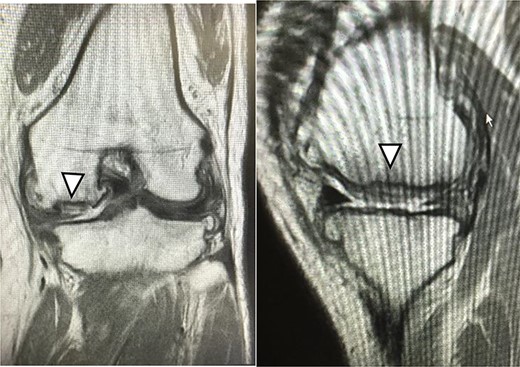

MRI findings at 1 year after the surgery indicated signal intensity area in the grafted area for the patient with JACC (Fig. 8), whereas the patient who underwent Reveille CP exhibited greater thickness at the grafted area as compared to the surrounding healthy cartilage (Fig. 9). The MOCART score at 1 year after the Reveille CP surgery (60 points) was higher than that of JACC (50 points).

One year after JACC, MRI showed T2 high intensity area in the graft area (arrowhead).

A new product development of ACI with Reveille CP has three characteristics. The first characteristic is that Reveille CP creates autologous tissue with more surface area to absorb bioactive factors available within the marrow stimulation superclot. The second characteristic is that it creates autologous tissue grafts that retain high levels of variable, biologically competent chondrocytes. The third characteristic is that it creates autologous tissue grafts that support cellular proliferation, migration and new tissue matrix formation in culture. The adaptation in size of the cartilage defect is up to 4 cm2 for Reveille CP and 4 cm2 or higher for JACC. The advantage of Reveille CP includes one-stage surgical technique that requires no allergic test for atelocollagen gel nor periosteum sacrifice when compared with JACC. Meanwhile, Adachi et al. [17] reported that clinical data improved significantly postoperatively after implantation of tissue-engineered cartilage for full-thickness cartilage defects of the knee. In addition, good clinical outcomes were maintained for at least a median of 8.0 years, indicating the efficacy and durability of this procedure. Also, the MOCART score in case 2 improved to 75 points at 5 years after JACC surgery (Fig. 10). Knutsen et al. [18] revealed that further surgery was required in 23% of patients at 69 months after both ACI and microfracture treatments. In other words, a long-term follow-up of ACI using Reveille CP is required.